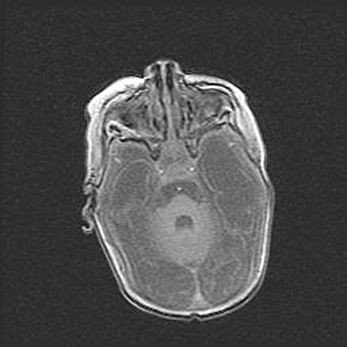

Мальформация Денди-Уокера. Киста задней черепной ямки.

Агенезия мозолистого тела.

Возраст: 2,5 месяца

Вес: 2420 г

Пол: женский

Окружность головы: 37 см

Срок гестации: 32 недели

Мальформация Денди—Уокера — редкий вид патологии ЦНС, представляющий собой врожденный порок развития каудального отдела ствола и червя мозжечка, ведущий к неполному раскрытию срединной (Мажанди) и латеральных (Лушка) апертур IV желудочка мозга. Для этогно синдрома характерна триада симптомов: гипотрофия червя мозжечка и/или полушарий мозжечка, кисты задней черепной ямки, гидроцефалия различной степени. В 70% случаев порок сочетается и с другими аномалиями головного мозга, в частности с агенезией мозолистого тела.